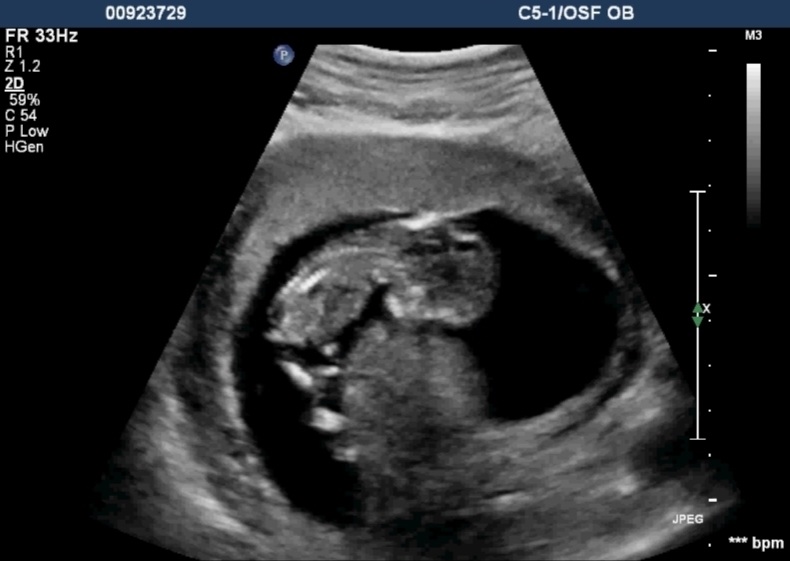

I know it is early and this isn't a great pic, but any thoughts on gender? I was 12 weeks, 1 day.

Yeah I wasn't given any good profile shots.:-/ Here's what I have...Attachment 12408Attachment 12409Attachment 12410